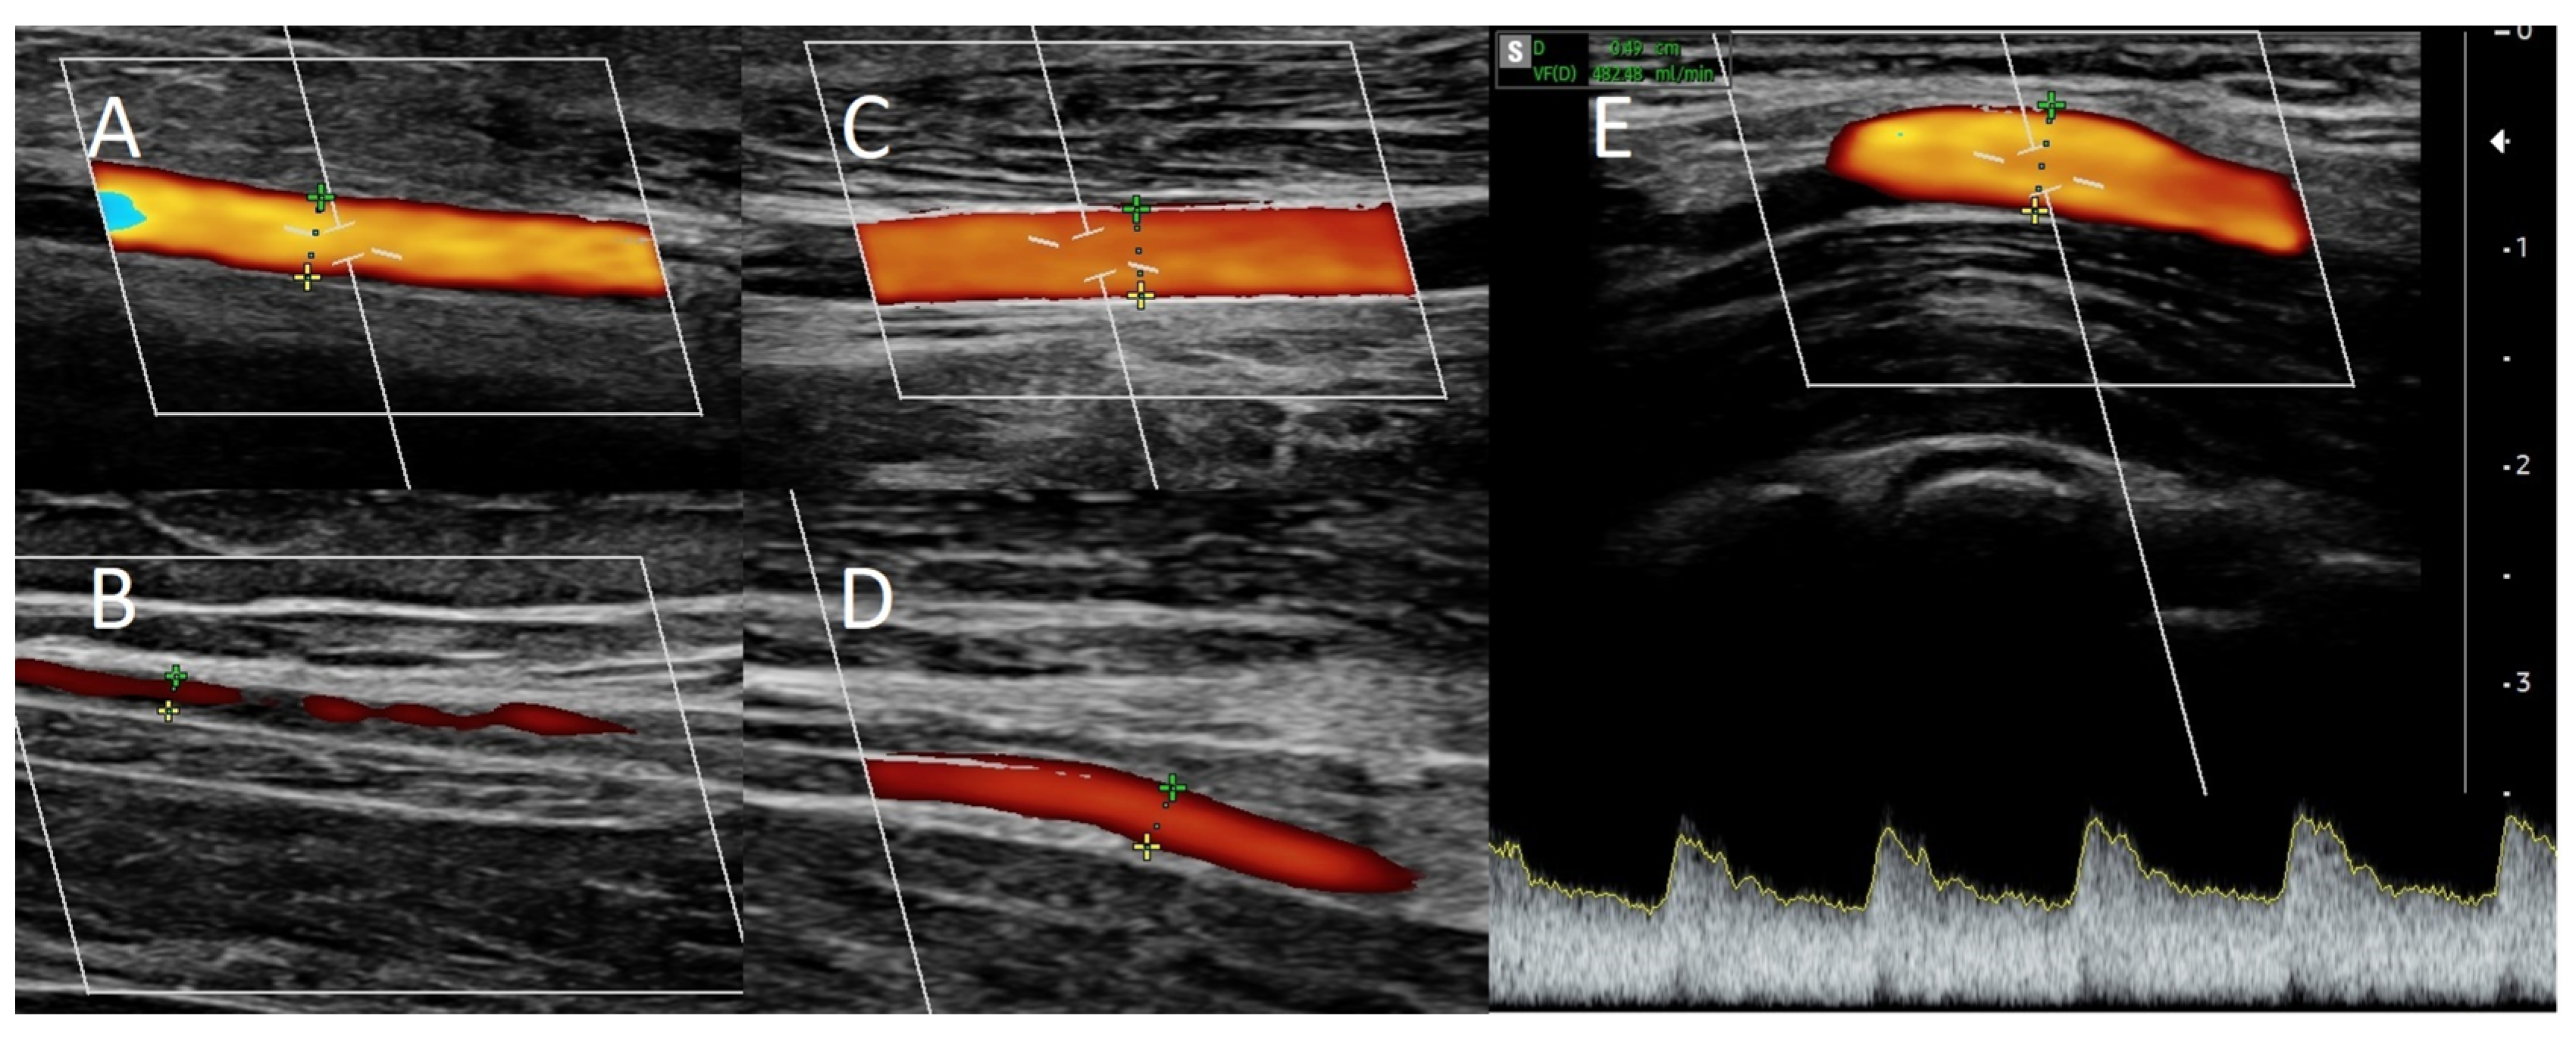

Figure 3.

Doppler ultrasound (A) of the ulnar artery before RADAR intervention, (B) of the radial artery before RADAR, (C) of the ulnar artery after RADAR, and (D) of the radial artery after RADAR. (E) Blood flow in brachial artery after RADAR intervention.

Local anesthesia consisting of 1% lignocaine solution was used during the procedure. An oblique incision was made in the distal part of the forearm, approximately 2 to 3 cm proximal to the primary fistula (Figure 2B). The appropriate vessel fragments were dissected. Over the ligature, the radial artery was severed, and the blood supply was verified by momentarily releasing the clamp. The perceived blood flow was satisfactory. The cephalic vein was then clamped both distally and proximally, and, finally, it was subsequently incised longitudinally. The vein and artery were flushed with heparinized saline, and approximately 5000 IU of unfractionated heparin was administered. Both vessels were sutured with a continuous suture, i.e., the end of the artery was anastomosed with the side of the vein using a non-absorbable polypropylene vascular suture of 6-0 (Figure 2B). During the procedure, the operator used a magnifying glass with 2.5 times magnification. Option I for anastomosis (Figure 1) was used in this case due to the long RA and the wide segment between the RA and CV. The vein filled with blood when the clamps were removed, and a typical murmur was noticed (Figure 2B). The wound was closed with skin sutures. Ultrasound examination confirmed that the fistula was patent the day following the procedure. UA and RA diameter was 4 mm and 2 mm, respectively (Figure 3C,D). The blood flow rate through the UA was 193 mL/min (Figure 3C), while the brachial blood flow rate was 482 mL/min (Figure 3E). The patient was discharged with a fistula that was functional. Neither anticoagulants nor antiplatelet medications were administered to her during the postoperative period. At the 3-week postoperative follow-up appointment, the fistula remained patent, and the first successful cannulation was performed 4 weeks after surgery (Figure 2C).